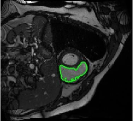

4.3 Comparison with cardic MR images for right ventricle segmentation

Cardiac MRI images often suffer from intensity inhomogeneity due to the varying magnetic susceptibility of cardiac tissues. This can lead to ambiguous boundaries, making it hard for models to consistently identify the left ventricle. Moreover, the heart is composed of several complex anatomical structures, including chambers, valves, and surrounding tissues. Accurately delineating the borders between these various components can be difficult, especially when they are closely positioned or exhibit similar intensity characteristics. In this section, we demonstrate the effectiveness of the RefLSM in segmenting cardiac MR images. The cardiac MR images are standardized to a size of . To enhance the credibility of the proposed model, we segmented 5 cardiac MR images compared the results with 6 other models, including the ALF [MA2019201], LoGRSF [DING2017224], ABC [WENG2021115633], RESLS[8765635], ICTM [WANG2022108794] and FeaACM [XUE2024110673] models. Fig. 5 displays the partial results from all the segmentation models. It is clear that the segmentation results from the RefLSM closely align with the ground truth of the left ventricle segmentation. However, the ALF model demonstrates relatively poor ability to capture the overall structure of the left ventricle; it exhibits limitations with precise boundary detection, particularly in areas of intensity inhomogeneity. Consequently, the evolution curve of the ALF fits into an unstable wave-like result. Suffering from intensity inhomogeneity and surrounding anatomical structures, the LoGRSF model, ABC model and RESLS model all represent over-segmentation and under-segmentation to some extent. Additionally, the results in the 6th column of Fig. 5 show multiple instances where where the ICTM model inaccurately identifies adjacent myocardial tissues as part of the left ventricle due to their similar intensity, leading to false positives. While the FeaACM demonstrates some ability to segment the left ventricle, it is not robust and fails to segment the 5th row of Fig. 5. The 2nd and 3rd rows also include small adjacent excessive regions. In contrast, our proposed model demonstrates marked improvements in accurately capturing the left ventricle’s boundaries. It effectively addresses challenges associated with severe intensity inhomogeneity and noise, resulting in better segmentations. The proposed method appear to maintain better structural integrity in the segmented images, closely aligning with the ground truth.

To quantitatively measure the segmentation results of each model, we compute the Dice and Precision values for left ventricle segmentation. Moreover, we opted for a voilin plot to effectively compare the RefLSM with six other models, as shown in Fig. 7. The results clearly demonstrate that the RefLSM yields superior Dice and Precision values than the other representative models, indicating its closer alignment with the ground truth and highest segmentation accuracy.